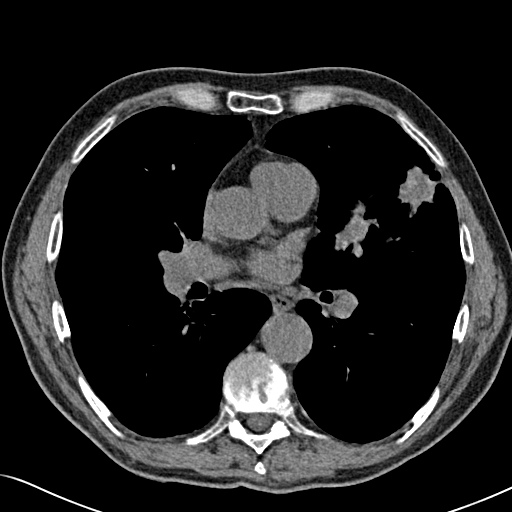

Choose if image shown above is Real or Fake :

Real

Fake